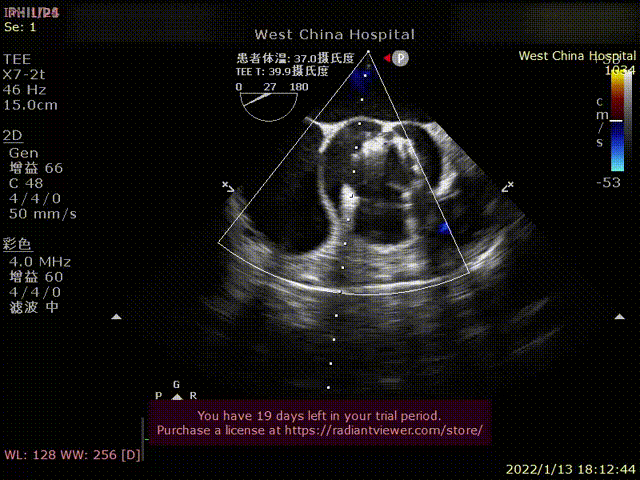

患者为68岁男性,因“胸闷、气促4余年,加重一年”主诉入院。术前超声心动图提示:左心增大,左室为著,左室壁肥厚,LVDD90 mm,LVEF35%,主动脉瓣右冠瓣脱垂、重度反流。术后即刻主动脉瓣大量反流消失,LVDD缩小至84 mm,左室较术前明显缩小。

术前超声影像